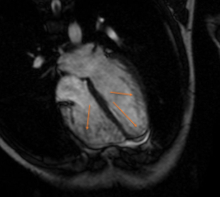

Abstract Body (Do not enter title and authors here): A 16-year-old-male presented in 2016 after a fall with a concussion due to dizziness. Chest X-ray showed a prominent cardiac silhouette. Further workup showed an echocardiogram with no left ventricular hypertrophy and mild left ventricular dilation. A Holter monitor recorded 1259 single PACs and 87 aberrantly conducted PACs. The patient was diagnosed with anxiety in 2017 and started on sertraline and later changed to fluoxetine. These medications were stopped at the end of 2022. In early 2023, he presented with symptomatic sinus bradycardia. A coronary angiogram revealed no obstructive CAD. MRI showed LV noncompaction towards the ventricular apex. Genetic testing showed a heterozygous HCN4 gene mutation.

The HCN4 gene mutation variants affect the cyclic nucleotide-gated cardiac ion channels, potentially leading to arrhythmias. It is most associated with patients with sinus node dysfunction. Specific mutations have been known to also present with left ventricular noncompaction (like in our patient), sick sinus syndrome, and susceptibility to ventricular fibrillation. Emerging evidence suggests that HCN4 gene may have potential expression in the brain. It is known that the HCN1 and HCN2 genes are common in the brain, but they are finding that the HCN4 gene is used as an “on-off” button that can control the way neurons respond to synaptic input.